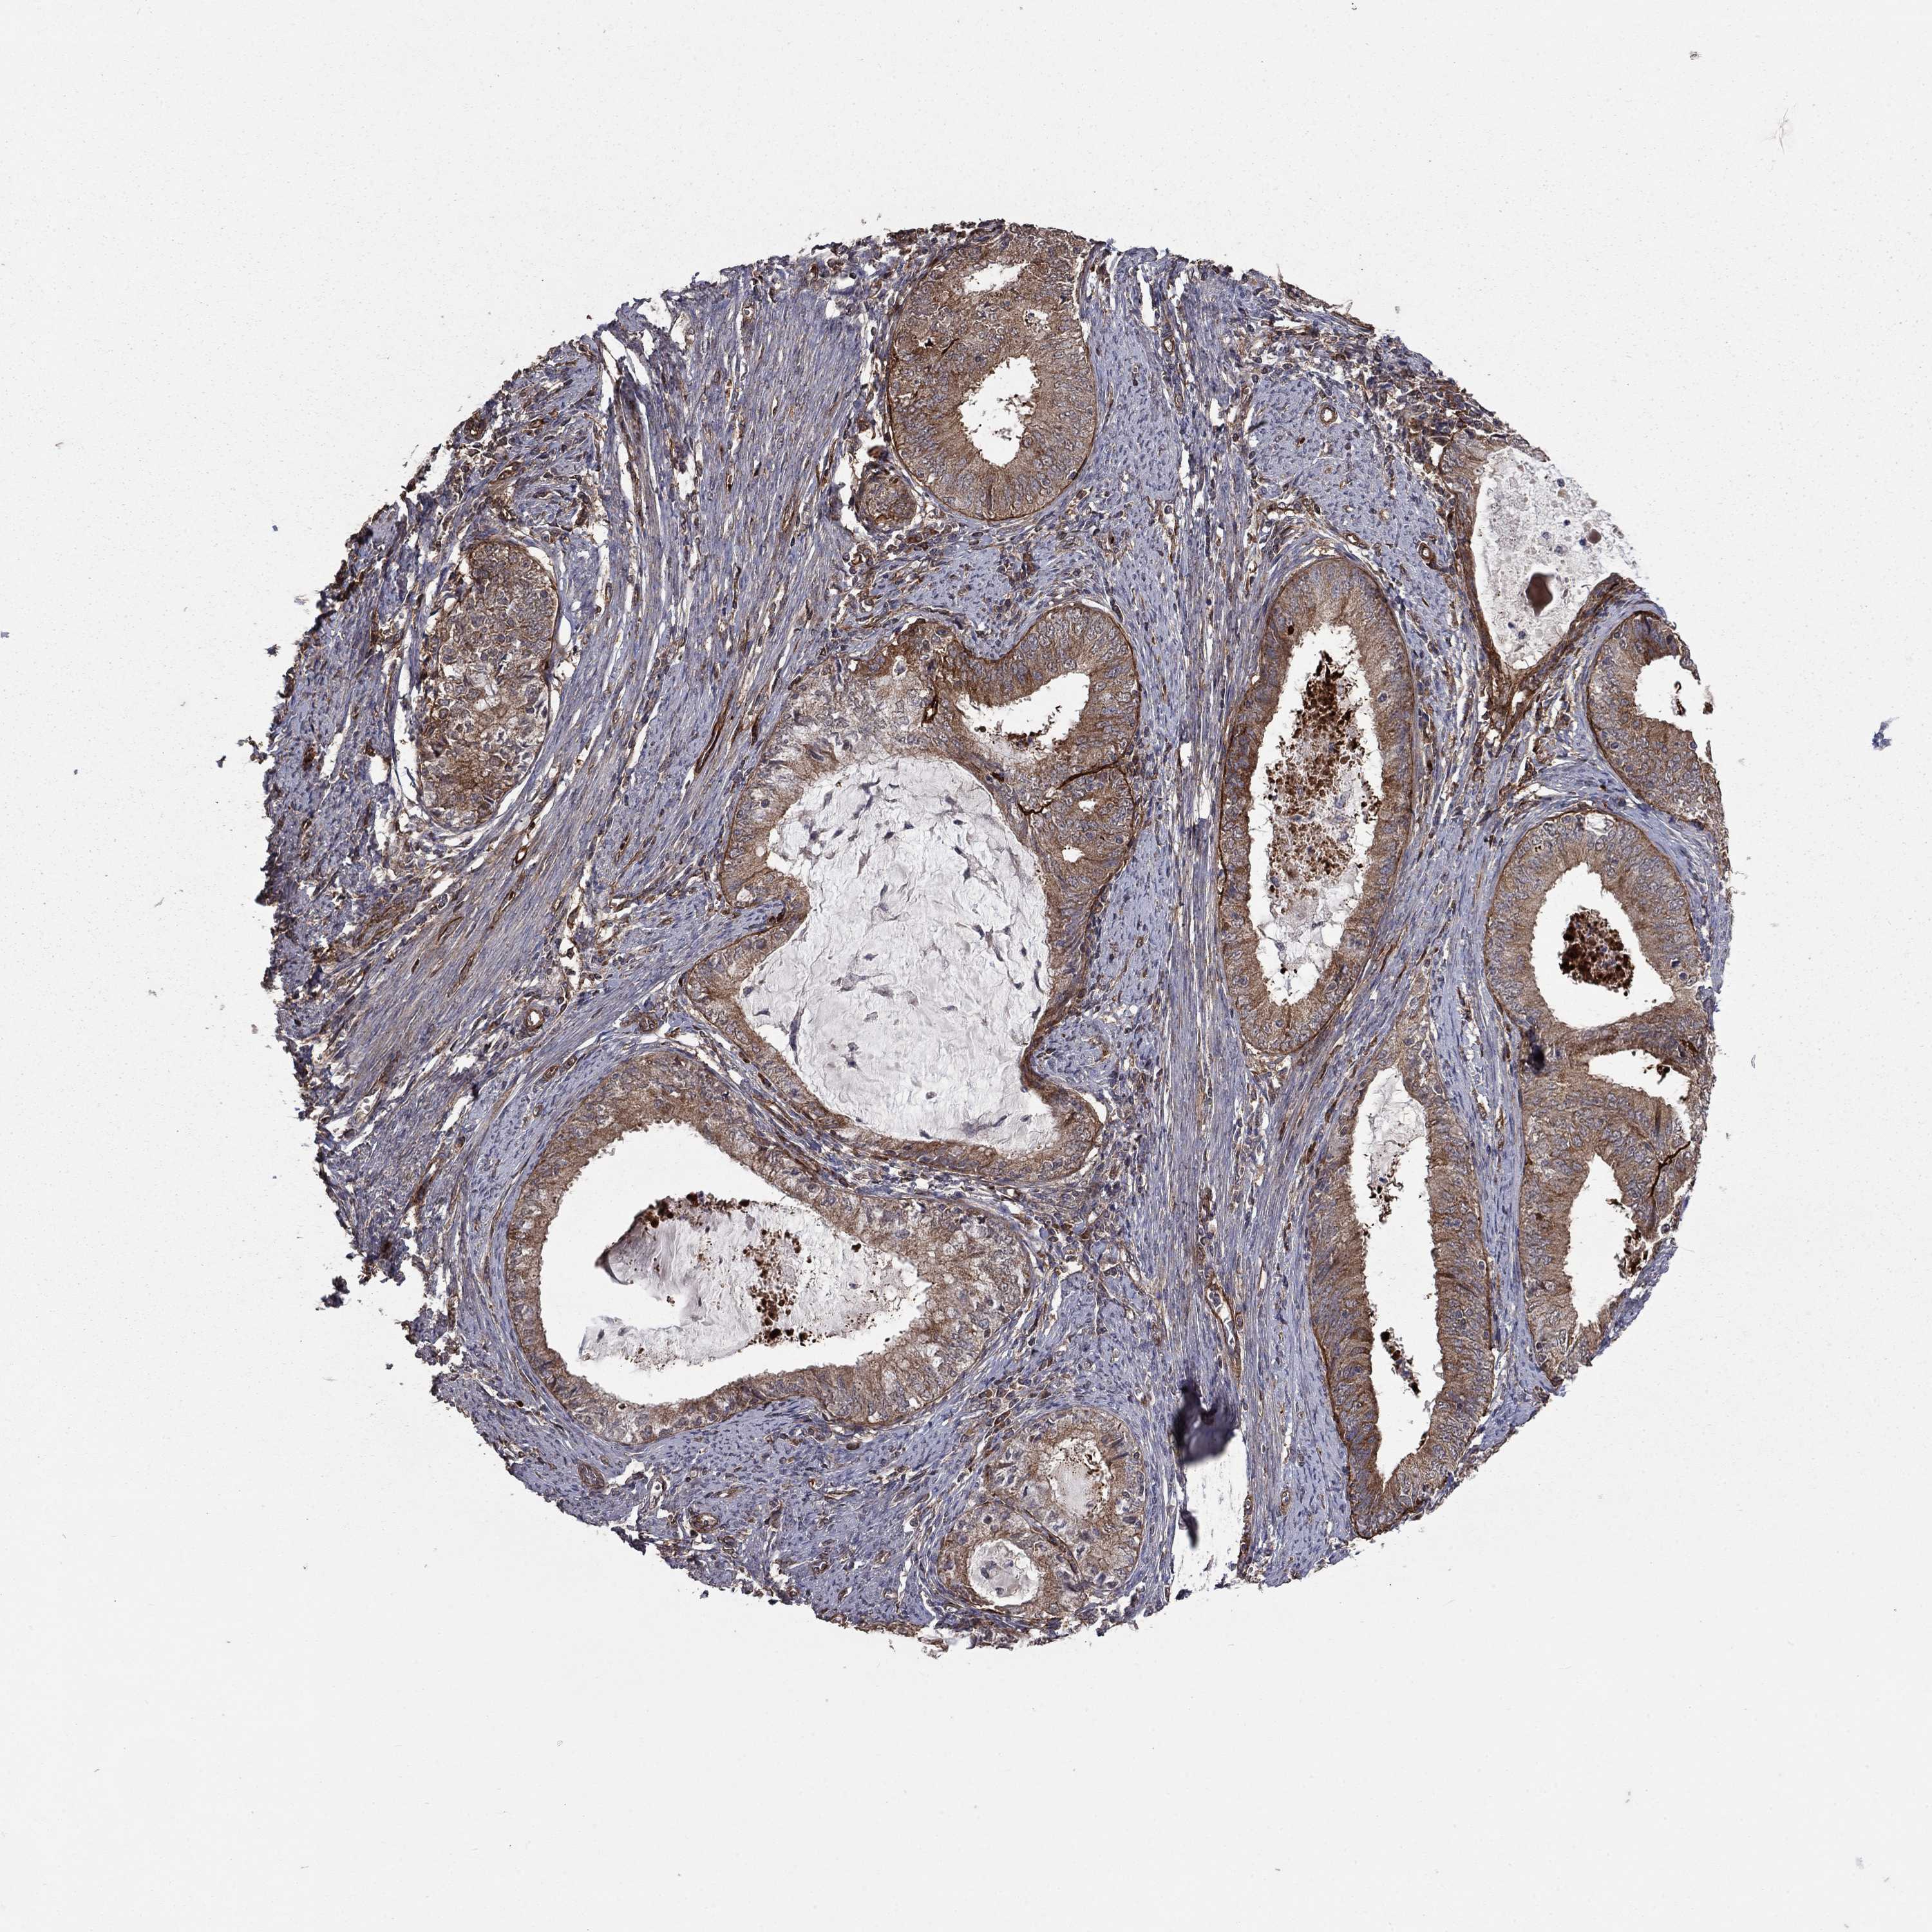

ENDOMETRIAL CANCER - Protein expressioni

A mouse-over function shows sample information and annotation data. Click on an image to view it in a full screen mode. Samples can be filtered based on level of antibody staining by selecting one or several of the following categories: high, medium, low and not detected. The assay and annotation is described here.

Note that samples used for immunohistochemistry by the Human Protein Atlas do not correspond to samples in the TCGA dataset.

Antibody stainingi

Antibody staining in the annotated cell types in the current human tissue is reported as not detected, low, medium, or high, based on conventional immunohistochemistry profiling in selected tissues. This score is based on the combination of the staining intensity and fraction of stained cells.

Each image is clickable and will lead to virtual microscopy that enables deeper exploration of all samples and also displays staining intensity scores, fraction scores and subcellular localization as well as patient and tissue information for each sample.

Antibody HPA030933

Staining

High

Medium

Low

Not detected

Intensity

Strong

Moderate

Weak

Negative

Quantity

>75%

75%-25%

<25%

None

Location

Nuclear

Cytoplasmic/membranous

Cytoplasmic/membranous,nuclear

Adenocarcinoma, NOS